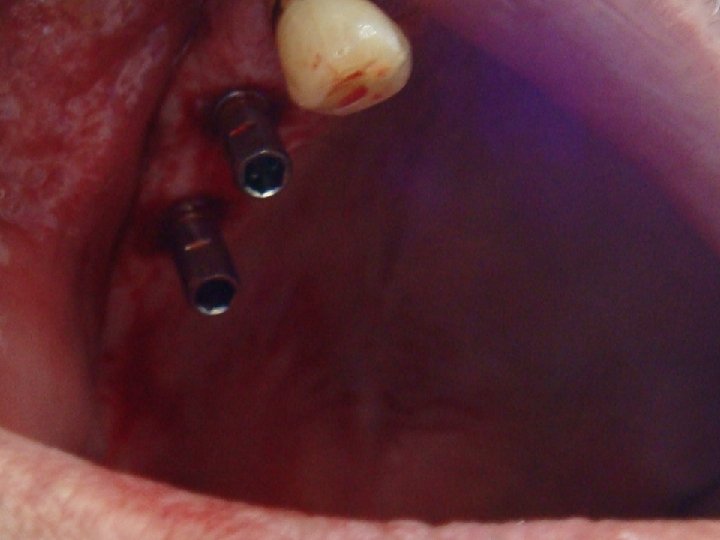

Abstract No. 1: A great challenge in implantology today is a predictable, long lasting red aesthetic result. An innovative treatment concept is based on a non-traumatic and effective shaping of the periimplant soft tissue – including an anatomical shaping from the first second. Especially, too many assembling and removing of abutments can contribute to aesthetic complications by vertical tissue loss. Therefore the “one abutment one time” and the “one crown one time” concepts are preferred. Additionally, platform switched and sealed implant-abutment connection prevent crestal bone loss and an apical shift of mid facial soft tissue.

Abstract No. 1: (cont. . ) In case of a fresh extraction socket the seal with the own tooth or a temporary crown can keep the complete soft tissue shape in a easy and predictable way. This "prosthetic" socket preservation simulates an intentional tooth reimplantation without the root. The same seal and therefore an optimal healing mode of the extraction socket is realized by an immediate implant insertion and restoration.

Abstract No. 1: (cont. . ) The lecture demonstrates a workflow for oral surgeons, prosthodontists and dental technicians to achieve a predictable midfacial soft tissue level by an effective and non traumatic protocol. Primarily results of a prospective clinical trial are promising. Additionally an insight into a scientific based explanatory model is given how a stable conical connection can increase the probability of a periimplant tissue preservation.